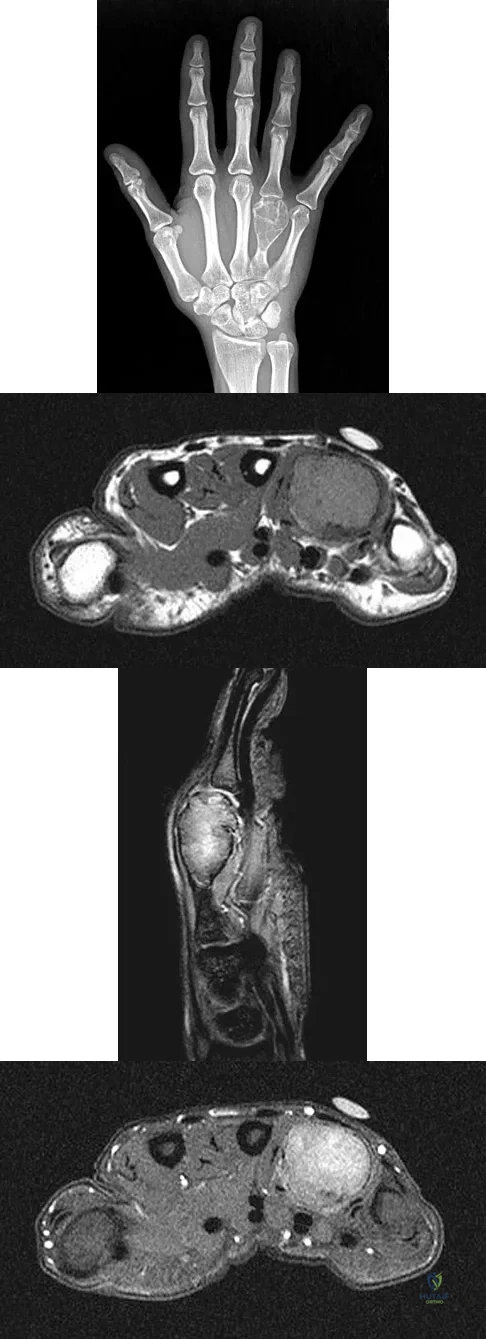

Question 82

A 26-year-old man has had hand pain and progressive swelling in the knuckle for the past several months. He denies any trauma to the hand. The ring finger metacarpophalangeal joint is tender, and there is loss of motion in the digit. Figure 32a shows the radiograph and Figures 32b through 32d show the T1-weighted, T2-weighted, and gadolinium MRI scans, respectively. What is the most likely diagnosis?

Explanation